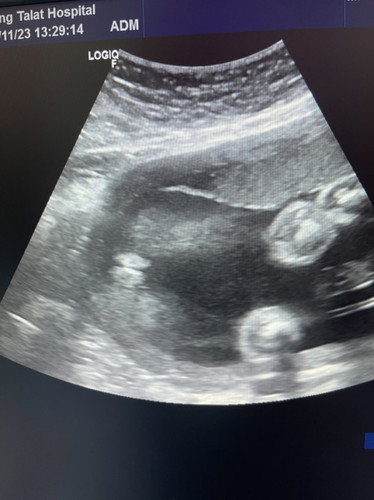

แบบนี้ผู้ชายหรือผู้หญิงค่ะ

ตอน5และ6เดือนหมอบอกผู้ชายค่ะแต่ตอนนี้7เดือนหมอมาบอกว่าผู้หญิงอยากทราบว่าแบบนี้ผู้หญิงจริงไมค่ะอยากซื้อชุดรอตัวน้อยแล้วค่ะ

เราก็ว่าน่าจะผู้หญิง ไม่มีอะไรโผล่มา😁

ผู้หญิงไหมคะ